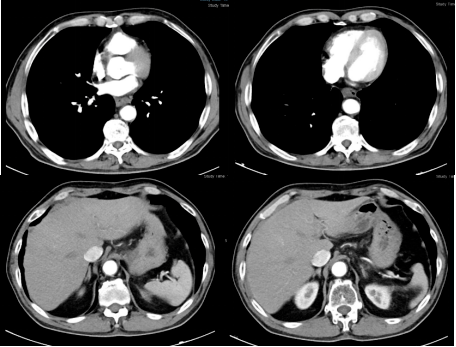

胸腹部ct:食管中下段管壁增厚,考虑食管癌;两肺多发结节影,纵隔及双侧

图片尺寸619x482